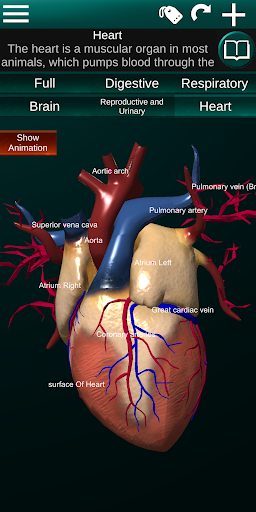

* Jantung, yang meliputi atrium, ventrikel, aorta, dan animasi organ ini.